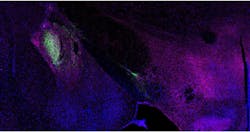

Using optogenetics, which is a technique where light activates these neurons, the researchers stimulated the terminal projections of the CeA-NTS neurons in the parabrachial and found that this stimulation inhibited the neurons in the parabrachial. When the scientists stimulated this projection with a laser in one half of the animal's box, animals would spend more time where the stimulation would occur.